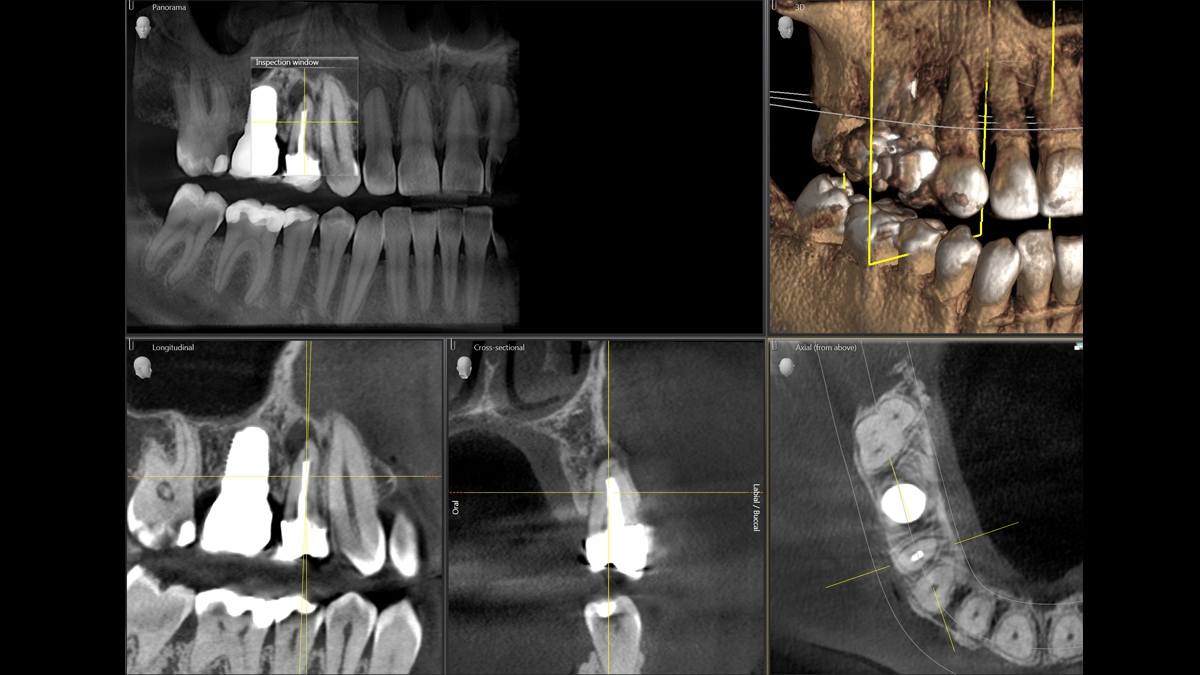

With the Axeos, the Orthophos SL 3D and the Orthophos S 3D from Dentsply Sirona, several hundred individual images are produced when taking a 3D X-ray in the space of just a few seconds. Using this data, the software generates a 3D image of the jaw area. The practitioner is then able to take a "virtual tour" of the scanned volume and assess the data from every dimension.

Gallery of Sample 3D Images